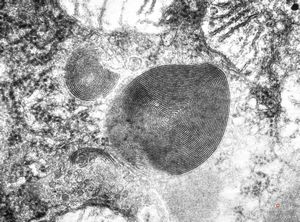

M,15y. | megamitochondria with lamellar inclusions in hepatocyte - Wilson disease